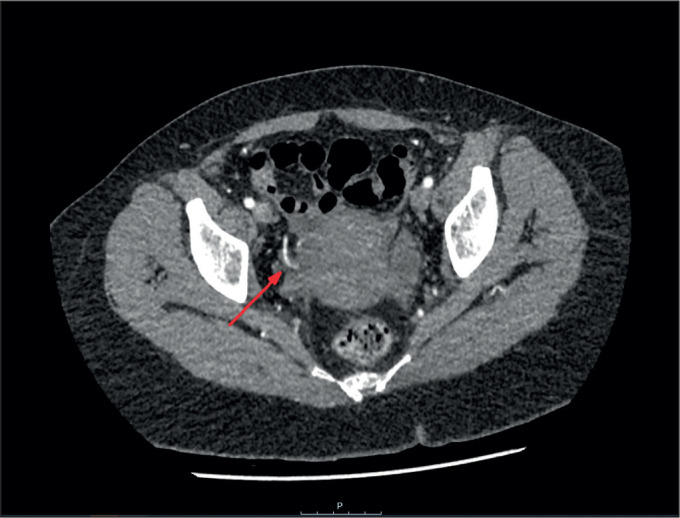

Spontaneous rupture of a uterine artery is a rare occurrence and more often associated with postpartum haemorrhage. It is even more unusual outside pregnancy. In this report, we will describe a case of spontaneous uterine artery rupture in a 40-year-old non-pregnant female with adenomyosis who presented with severe vaginal bleeding. We will also review the aetiology of rupture of uterine artery based on the current literature.